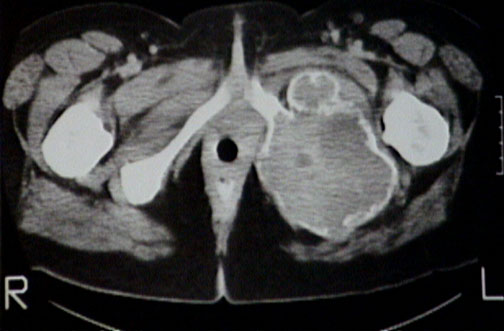

This is a computed tomographic (CT) scan of a giant cell tumor involving the left ischial ramus. The tumor is an eccentric, expansile, lytic mass with extension into soft tissue along with overlying reactive new bone formation.